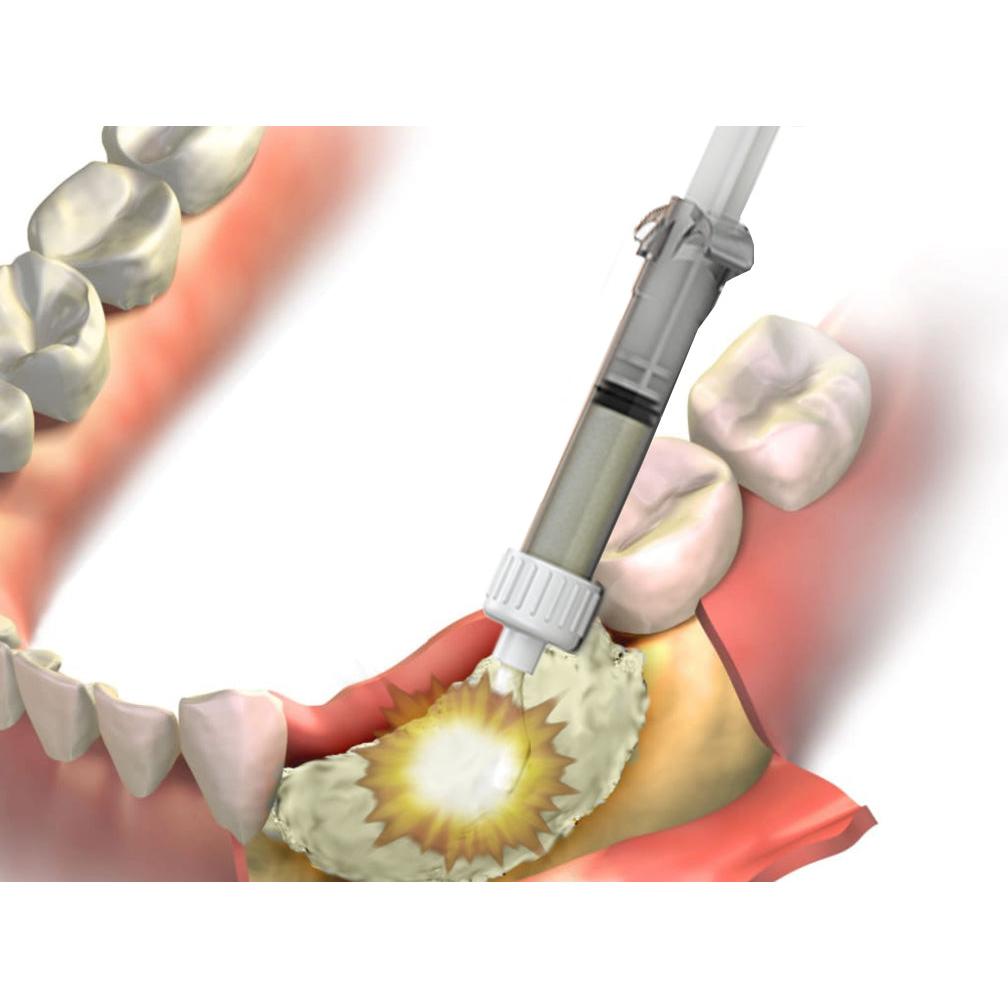

RESTORATIVE DESIGN & PRACTICAL OCCLUSIO… Robert M. Zupnik。RESTORATIVE DESIGN & PRACTICAL OCCLUSIO… Robert M. Zupnik。Reficio™ 100 Advanced DBM Fiber Putty Syringe, Curved - 1.0。「RESTORATIVE DESIGN & PRACTICAL OCCLUSION 実践的咬合」本多 正明定価: ¥ 330001年ほど前に新品購入し、一度読んで本棚に並べていました。。Functional Occlusion in Restorative Dentistry and。カバーやケースに多少の傷やスレはありますが、通読に支障をきたすような汚れや破れなどはありません。#本多正明 #本多_正明 #本 #自然/医療・薬学・健康